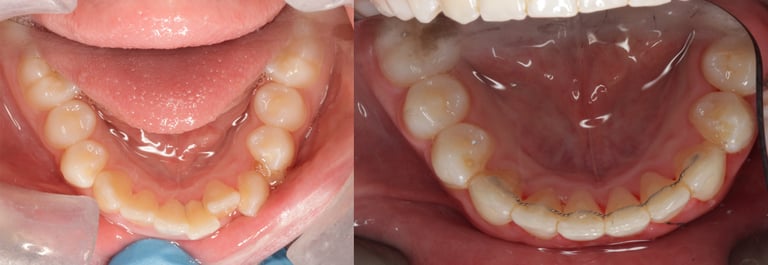

Aligner case 1

This patient in their early 30s didn't like how her crowded lower incisor could be seen when she was talking. Initially, she asked if it could be filed down as it looked longer. I reassured her that once the crowding was managed, the tooth would be the same level as the others. Treatment took around 9 months using Invisalign. Fixed retainers were placed after treatment to reduce the risk of the teeth moving back